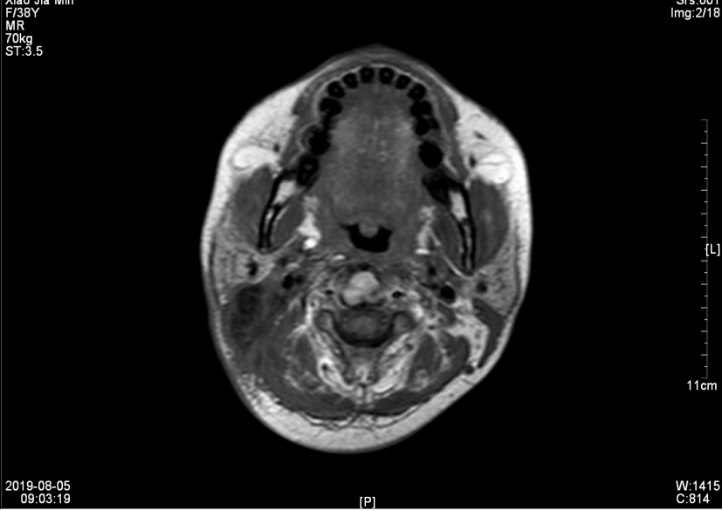

查【EB病毒五项】EB病毒VCA抗体(IgA) 阳性(+),EB病毒壳抗原(VCA)IgG抗体 阳性(+),EB病毒核抗原(EBNA1)IgG抗体 阳性(+),EB病毒早期抗原(EA)IgG抗体 阳性(+)。【肿瘤筛查1组(女)】糖链抗原CA-153 45.3U/ml。恶性肿瘤特异性生长因子 77U/ml。鼻咽MRI:1、考虑鼻咽癌,并侵犯周围结构及颅底骨质,伴右侧颈部、咽旁淋巴结多发转移(最大约60mm×49mm),请结合临床及其他检查。2、副鼻窦炎,右侧中耳乳突炎(见图一、二)。

▲图一 2019年1月19日 治疗前淋巴结MRI(60mm×49mm)

▲图二 2019年1月19日 治疗前鼻咽部肿块MRI